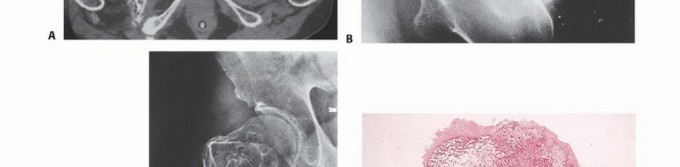

Radiographic and Advanced Imaging Modalities

- Plain Radiography: The cornerstone of initial evaluation. It accurately predicts the diagnosis in over 80% of extremity bone tumors. It defines the lesion's location, zone of transition (narrow/sclerotic = benign/slow; wide/permeative = malignant/aggressive), cortical destruction, and periosteal reactions (Codman triangle, onion-skinning, sunburst pattern).

- Computed Tomography (CT): The modality of choice for assessing fine osseous detail, cortical integrity, and matrix mineralization. Thin-slice (≤1 mm) helical CT allows for precise 3D reconstructions. Intravenous contrast is essential to delineate the relationship of the soft tissue mass to major vascular bundles. Chest CT is mandatory for staging to rule out pulmonary metastases.

- Magnetic Resonance Imaging (MRI): The gold standard for evaluating the local extent of the tumor. It accurately defines the intramedullary extent (allowing calculation of bone resection levels), soft tissue extension, joint involvement, and the presence of skip metastases. T1-weighted images best define marrow replacement; T2-weighted and STIR sequences highlight peritumoral edema and the soft tissue mass. Contrast enhancement differentiates cystic from solid components and clarifies neurovascular proximity.

- Bone Scintigraphy (Technetium-99m): Utilized to detect polyostotic disease and skeletal metastases. The three-phase bone scan assesses biologic activity; a "tumor blush" in the flow/pool phases indicates high vascularity typical of malignancy.

- Angiography and Venography: While largely supplanted by CT/MR Angiography, traditional angiography can map complex vascular displacements, identify feeding vessels for preoperative embolization (critical for hypervascular metastases like renal cell carcinoma), and assess the patency of collateral circulation prior to major vessel ligation. Venography can identify tumor thrombus or extrinsic venous compression.